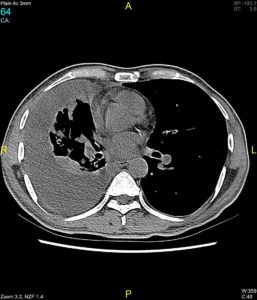

PET/CT: Useful in the staging of lymphoma with a sensitivity and specificity close to 100 %. Also useful in assessment of treatment response demonstrating residual metabolically active tumour and areas of necrosis and fibrosis. Primary breast cancers including inflammatory breast cancer and metastases, especially from melanoma, may be difficult to differentiate from haematopoietic neoplasms. There may be a false negative scan if the lesion is less than 1 cm.